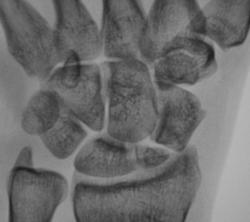

Катенёв Валенти... Дата публикации 13.10.2009, 18:16 Пациент направлен в рентгеновский кабинет хирургом для рентгенографии лучезапястного сустава. Травма. Произведено исследование. pp.1..JPG pp.2..JPG pp.3..JPG pp.4..JPG Ваше мнение коллеги? ВложениеРазмер pp.1..JPG62.4 КБ pp.2..JPG53.6 КБ pp.3..JPG95.92 КБ pp.4..JPG80.54 КБ Втр, 13/10/2009 - 21:14 #1 flagman Не на сайте Был на сайте: 11 лет 5 месяцев назад Зарегистрирован: 05.06.2008 - 20:08 Публикации: 83 странная ладья - неужели перелом? Втр, 13/10/2009 - 21:18 #2 Катенёв Валенти... Не на сайте Был на сайте: 7 лет 3 недели назад Зарегистрирован: 22.03.2008 - 22:15 Публикации: 54876 Один перелом "ладьи"? Втр, 13/10/2009 - 21:29 #3 Павел Владимирович Не на сайте Был на сайте: 16 лет 2 месяцев назад Зарегистрирован: 07.10.2009 - 20:47 Публикации: 11 перелом ладьевидной кости с расхождением отломков Втр, 13/10/2009 - 21:41 #4 Наталия Не на сайте Был на сайте: 8 лет 7 месяцев назад Зарегистрирован: 30.07.2008 - 13:24 Публикации: 538 Двойной перелом ладьевидной кости. Ср, 14/10/2009 - 07:52 #5 v1tal Не на сайте Был на сайте: 4 года 9 месяцев назад Зарегистрирован: 07.06.2008 - 19:41 Публикации: 1779 А как же полулунная ????? Ещё и ладья в предачу. "Знаешь, у некоторых врачей есть комплекс мессии — им необходимо спасать мир. А у тебя комплекс Рубика — тебе необходимо решать головоломки." Ср, 14/10/2009 - 14:38 #6 OPEXOB Не на сайте Был на сайте: 9 лет 11 месяцев назад Зарегистрирован: 26.07.2008 - 10:02 Публикации: 280 Может "снайперы" укажите стрелками, кто, что видет? Ср, 14/10/2009 - 19:48 #7 Глазков Игорь А... Не на сайте Был на сайте: 9 месяцев 2 недели назад Зарегистрирован: 19.12.2008 - 20:41 Публикации: 1597 ладьевидной кости Прийди к Себе

странная ладья - неужели перелом?

Один перелом "ладьи"?

перелом ладьевидной кости с расхождением отломков

Двойной перелом ладьевидной кости.

А как же полулунная ????? Ещё и ладья в предачу.